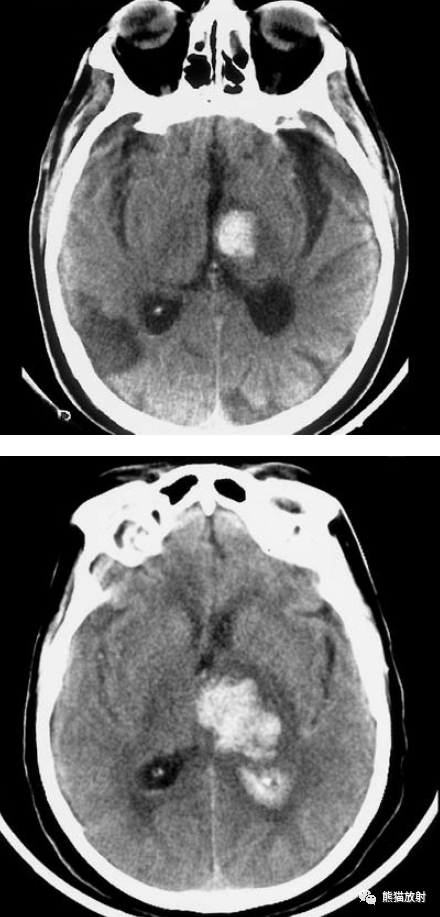

脑实质内出血的演变,分布,ct表现

ct平扫:左侧外囊和壳核大量高密度出血病灶,为典型的高血压性脑出血